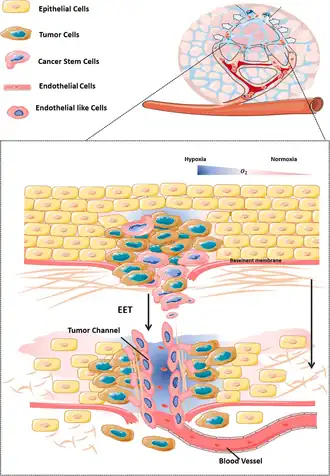

Vasculogenic mimicry (VM) is a strategy used by tumors to ensure sufficient blood supply is brought to its cells through establishing new tumor vascularization.[1][2][3] This process is similar to tumor angiogenesis; on the other hand vascular mimicry is unique in that this process occurs independent of endothelial cells. Vasculature is instead developed de novo by cancer cells, which under stress conditions such as hypoxia, express similar properties to stem cells, capable of differentiating to mimic the function of endothelial cells and form vasculature-like structures.[1][2] The ability of tumors to develop and harness nearby vasculature is considered one of the hallmarks of cancer disease development and is thought to be closely linked to tumor invasion and metastasis.[4] Vascular mimicry has been observed predominantly in aggressive and metastatic cancers and has been associated with negative tumor characteristics such as increased metastasis, increased tissue invasion, and overall poor outcomes for patient survival.[2][3] Vascular mimicry poses a serious problem for current therapeutic strategies due to its ability to function in the presence of Anti-angiogenic therapeutic agents. In fact, such therapeutics have been found to actually drive VM formation in tumors, causing more aggressive and difficult to treat tumors to develop.[5]

Hypoxia and tumor microenvironment

Another major mechanism through which vasculogenic mimicry is induced is hypoxia. Hypoxia is very common in tumors due to insufficient vasculature to provide oxygen for the rapidly proliferating tumor issues within what is known as the tumor microenvironment.[16] To circumvent this problem, tumors utilize a diverse set of pathways to promote various angiogenesis strategies as well as vasculogenic mimicry. Hypoxia inducible factors (HIFs) are transcription factors which are able to remain functional during hypoxic conditions, bind to hypoxia responsive elements (HRE) on the genome. Gene targets with HRE sites bind HIF and mediate gene transcription.[16] The location of HRE sites on the genome varies among cancer cell types, however hypoxia based signaling has been found to activate VM related genes including VE-cadherin, COX-2, Twist, Nodal, EphA2, VEGF-A, and VEGR-1.[7] Hypoxia can also promote VM through other signaling pathways such as NF-κB, which upregulates Twist expression, an inducer of VM.[6] It is important to note as well that many chemotherapeutic agents used in the treatment of cancers intentionally drive hypoxia in tumors as a treatment strategy by inhibiting tumor angiogenesis. While these treatments vary in efficacy depending on cancer type and patient, it has been shown that such therapies may actually drive tumors down more aggressive routes through the promotion of VM based tumor survival.[9]